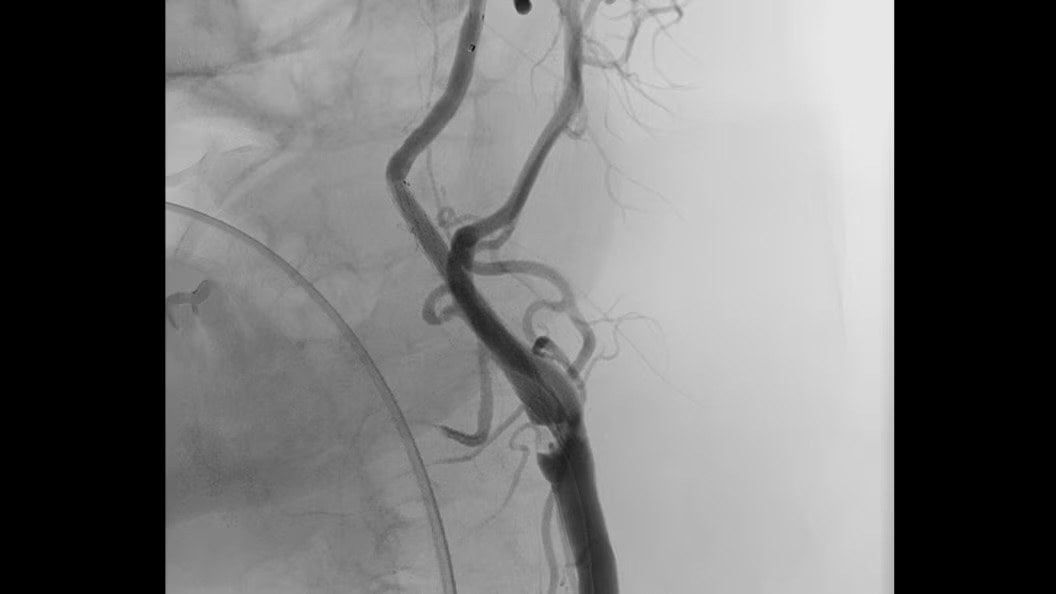

Cone-Beam Computed Tomography

Experience the precision of cone-beam CT, offering high-resolution 3D imaging for accurate diagnostics and treatment planning with enhanced safety and efficiency.